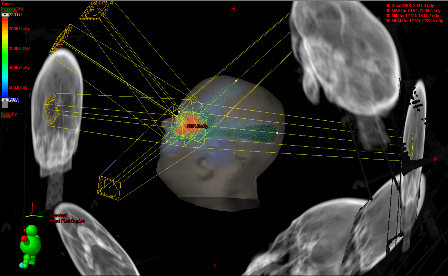

Esta técnica se basa en complejos sistemas informáticos de cálculo. La 3DCRT mejora la distribución espacial de la radiación ya que se adapta al volumen y forma del tumor mediante el uso de tomografías del paciente asociado a programas computarizados (TPS) y a la conformación del haz de radiación a través un Colimador Multiláminas (MLC).

Se puede así reproducir una imagen tridimensional fiel del tumor y los órganos vecinos de modo que el campo de radiación tenga el contorno exacto del área de tratamiento, logrando optimizar la dosis de radiación sobre la zona a tratar con protección del tejido sano, asegurándose la óptima cobertura del tumor, cualquiera sea su forma.

La 3D-CRT ha demostrado mejorar los resultados del tratamiento, comparado con la radioterapia convencional, en tumores de cerebro, cabeza y cuello, pulmón e hígado, entre otros.